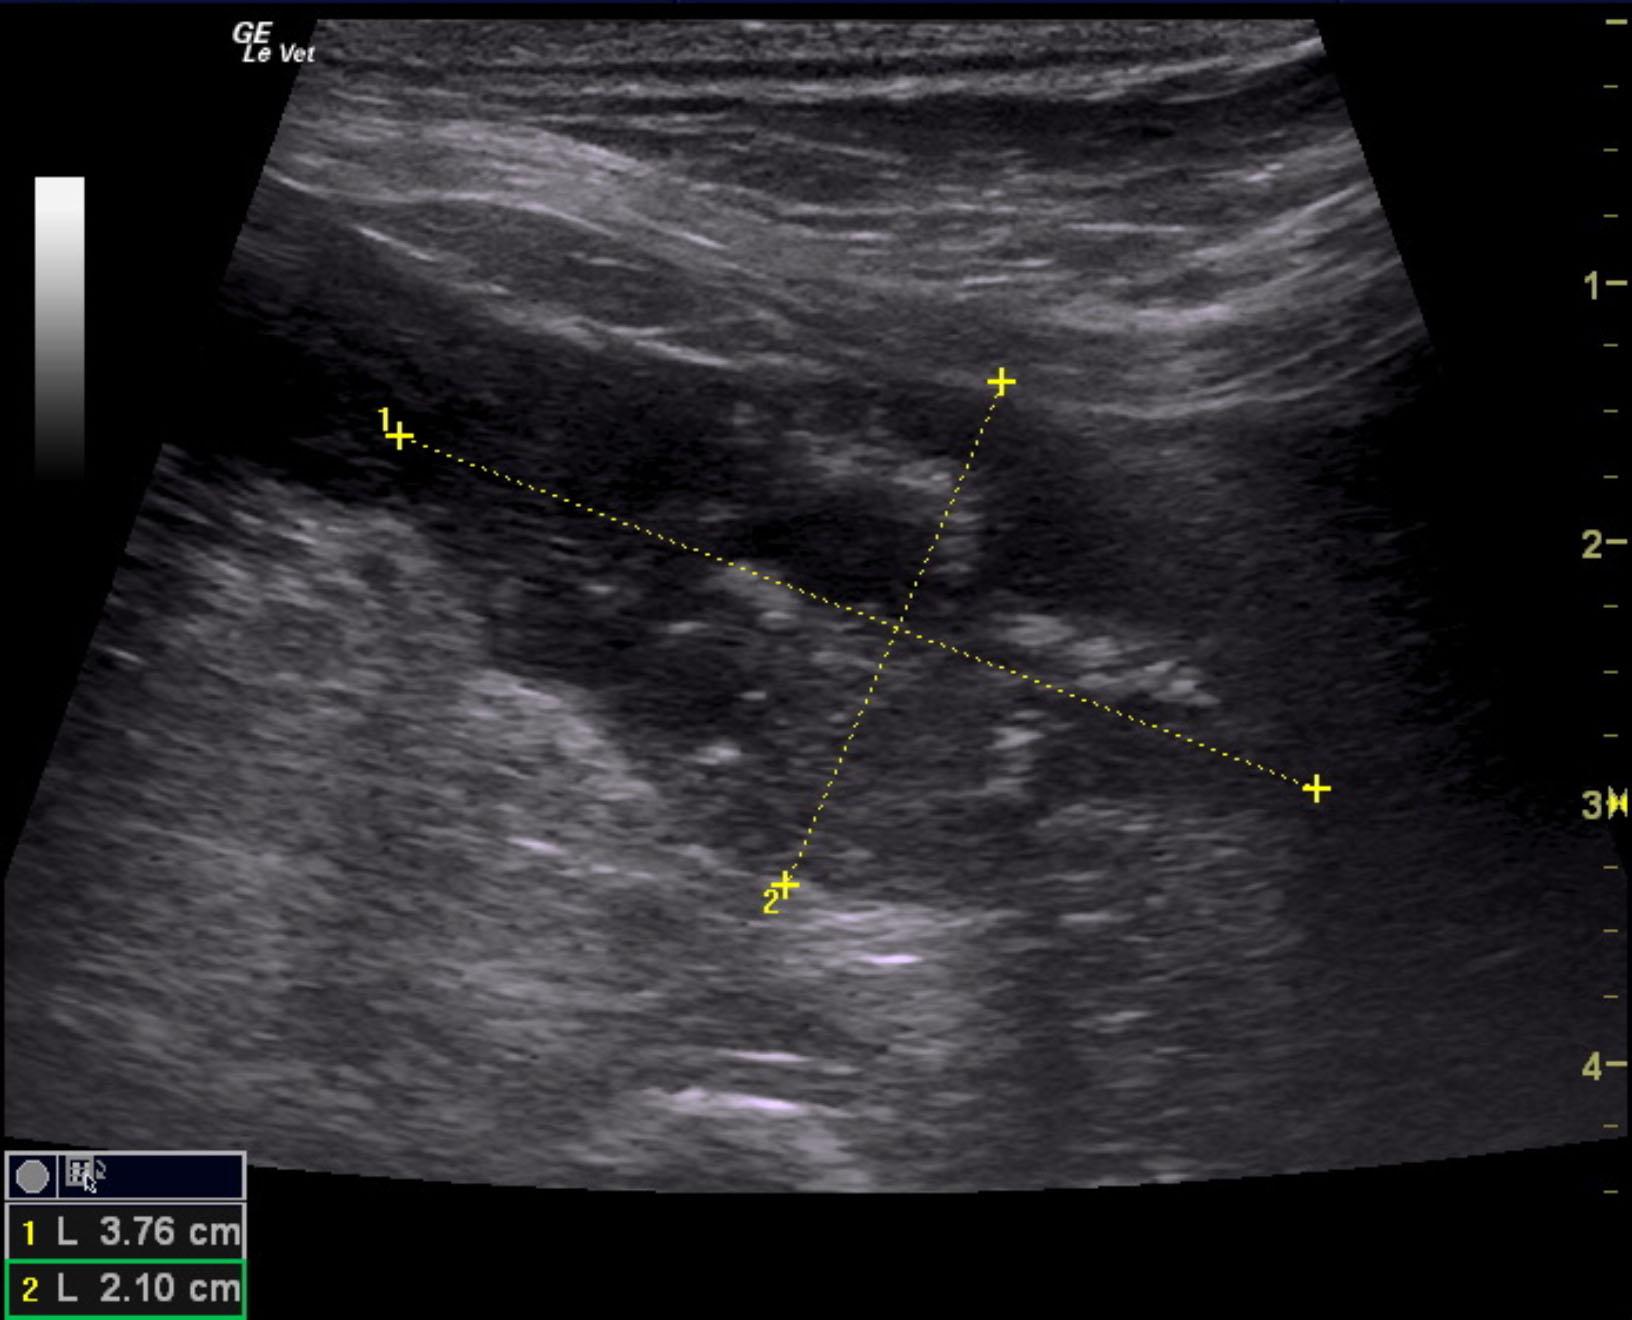

The prostate in this patient was enlarged with multi focal areas of mineralization. This is strongly suggestive for prostatic carcinoma. Ultrasound-guided FNA is recommended to confirm. Significant power Doppler vascularity was noted to the prostate. The prostate measured 3.76 x 2.1 cm with cauliflower projection into the cystourethral junction and invasion into the post prostatic urethra. Deviation of the descending colon was noted. This is owing to the prostatic pathology, which is responsible for the clinical signs.